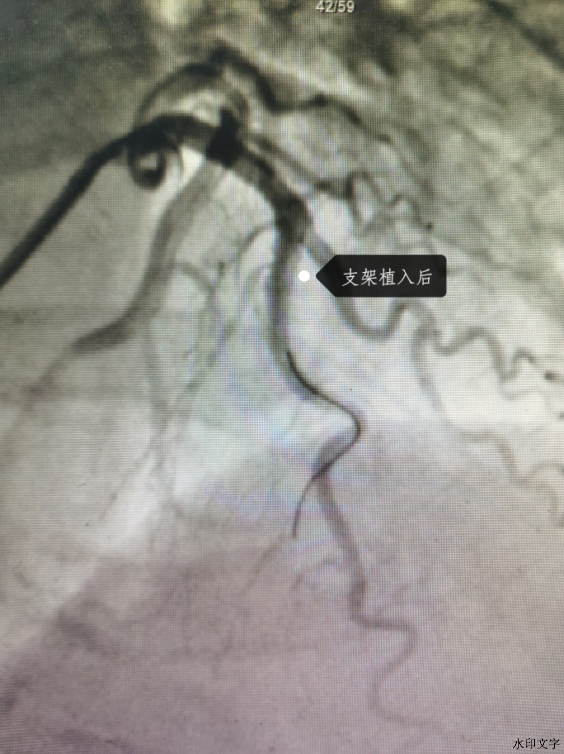

根据IVUS的测出的血管管腔大小给予植入3.0*30mm药物洗脱支架,取3.25*12mm非顺应性球囊送至左前降支病变段支架内,在支架内以18-20atm扩张塑形。再次行IVUS检查证实支架贴壁良好。